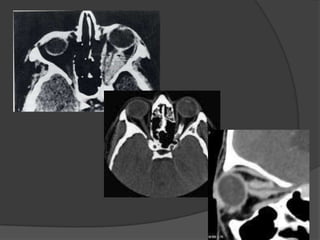

 CT Imaging

Findings:

 Imaging depends on the

macroscopic growth

pattern of the tumor.

 Allows good evaluation of

the optic nerve due to the

intrinsic contrast between

the nerve and the conal

fat.

 But is less sensitive

than MR imaging for

intracranial extension.

Optic Nerve Glioma:

 Fusiform enlarged

optic nerve.

 kinking or tortuosity of

its course.

 Iso- to slightly hypo

attenuation.

 May be eccentric or a

discrete mass seen

from the nerve.

 High attenuation or

calcification are rare.

 Enlargement of the optic

canal.

 Enhancement is

variable.

 Cystic tumors show

enhancement of its

wall.

Optic Nerve Glioma: CT Imaging Findings:  Imaging depends on the macroscopic growth pattern of the tumor.  Allows good evaluation of the optic nerve due to the intrinsic contrast between the nerve and the conal fat.  But is less sensitive than MR imaging for intracranial extension.

Optic Nerve Glioma: Fusiform enlarged optic nerve.  kinking or tortuosity of its course.  Iso- to slightly hypo attenuation.  May be eccentric or a discrete mass seen from the nerve.

Optic Nerve Glioma: High attenuation or calcification are rare.  Enlargement of the optic canal.  Enhancement is variable.  Cystic tumors show enhancement of its wall.